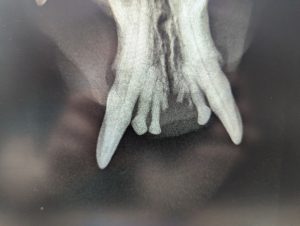

As you can see above, the incisors of this cat on the left are fully intact, with no signs of fracture or resorption. On the right, however, the incisors have snapped leaving the roots intact but invisible above the gum line.